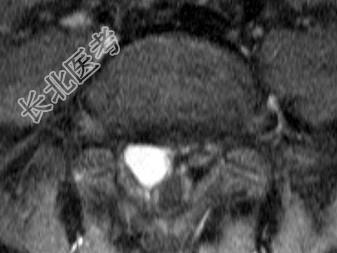

- 单项选择题男,8岁, 左髋疼痛,跛行1月余, 结合MRI检查,最可能的诊断是 ( )

A、骶部神经鞘瘤

B、室管膜瘤

C、神经纤维瘤

D、脊膜瘤

E、脊髓空洞症